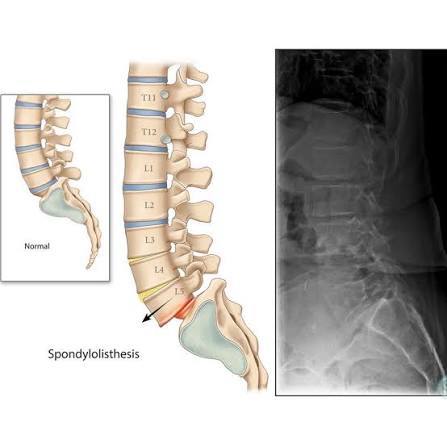

Спондилолістез — це зміщення одного хребця відносно іншого, найчастіше вперед (антеролістез), рідше назад (ретролістез). Тобто хребець «з’їжджає» зі свого місця, втрачаючи правильне розташування в хребтовому стовпі.

Так, спондилолістез (spondylolisthesis) — це реальний, офіційний медичний діагноз, який використовується у міжнародній класифікації хвороб МКХ-10 (код M43.1) та МКХ-11 (код FA80.0). ____ Як це виглядає__ На рентгені або МРТ видно, що: тіло верхнього хребця зміщене вперед або назад; міжхребцевий диск деформований або сплющений;

іноді видно дефект у дузі хребця (спондилоліз) — це причина нестабільності.